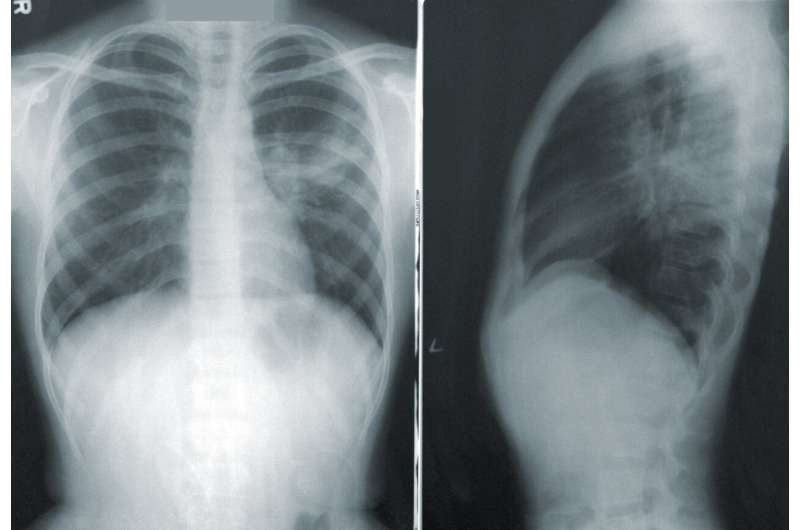

| Hình chụp phổi của bệnh nhân ung thư phổi |